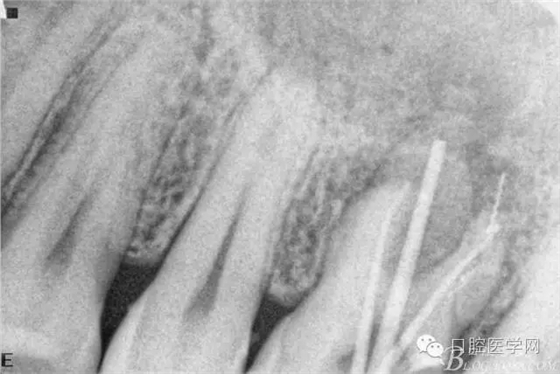

根充后三個(gè)月。

根充后四個(gè)月。根尖炎性陰影明顯減小,唯獨(dú)遺憾的是遠(yuǎn)頰根一斷針,不知后續(xù)如何,日后再行根尖手術(shù)吧。